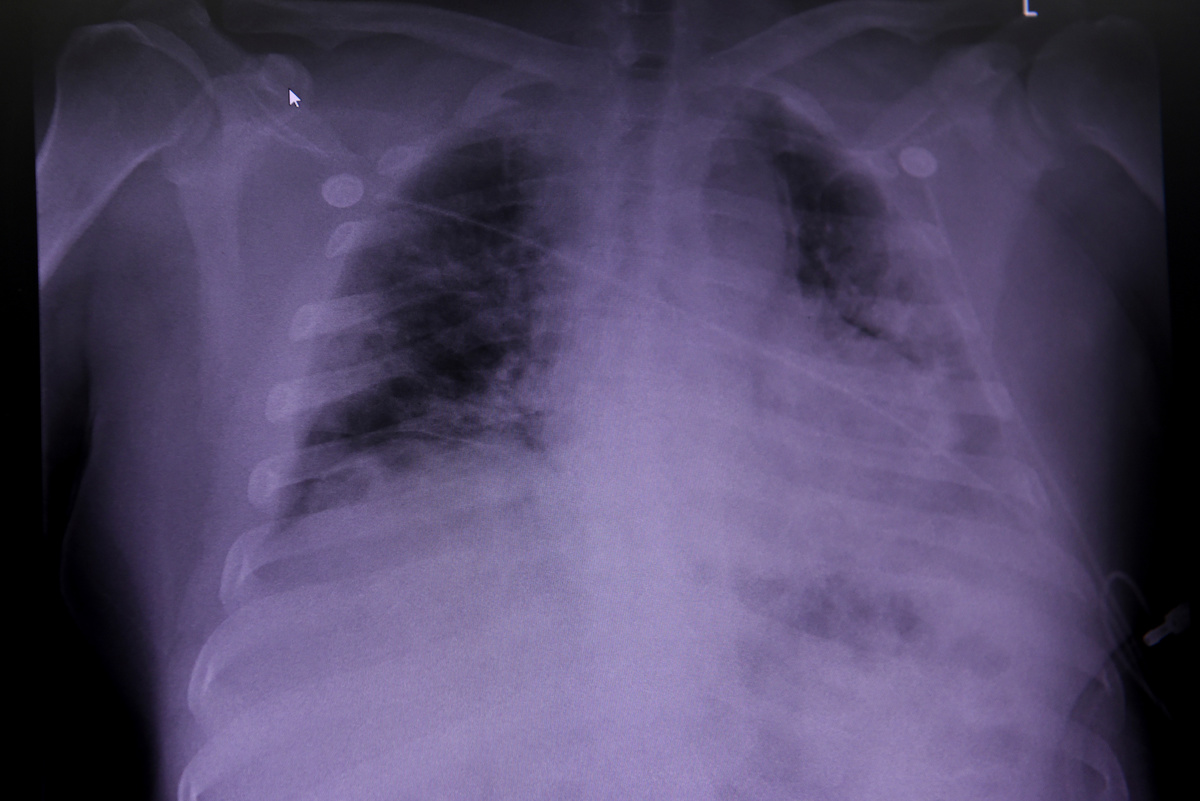

Earlier this month, Reuters followed the lung and critical care specialist on a shift as he hurried through the hallways - a small cohort of nurses and medical students in tow - pausing to inspect X-rays or medical charts and check on patients, at times offering them words of comfort or reaching out to hold their hand.

An X-ray of a COVID-19 patient's lungs is looked over by Dr. Joseph Varon (not pictured), the chief medical officer at United Memorial Medical Center (UMMC), during the coronavirus disease (COVID-19) outbreak, in Houston, Texas, U.S., July 10, 2020. REUTERS/Callaghan O'Hare